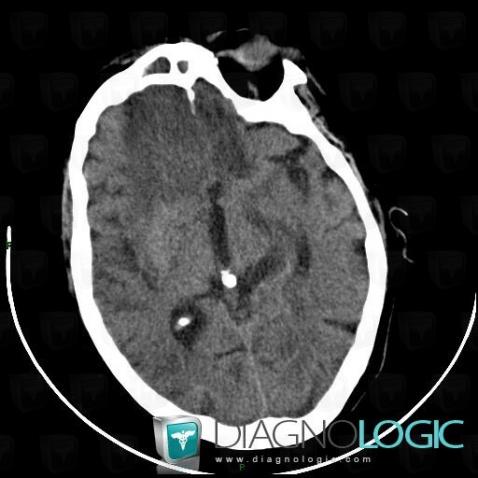

Encephalitis, Cerebral hemispheres, CT

Here is the specific information in the key image above:

- Diagnosis Encephalitis, Location(s) Cerebral hemispheres, with gamuts Intracerebral lesion with moderate enhancement